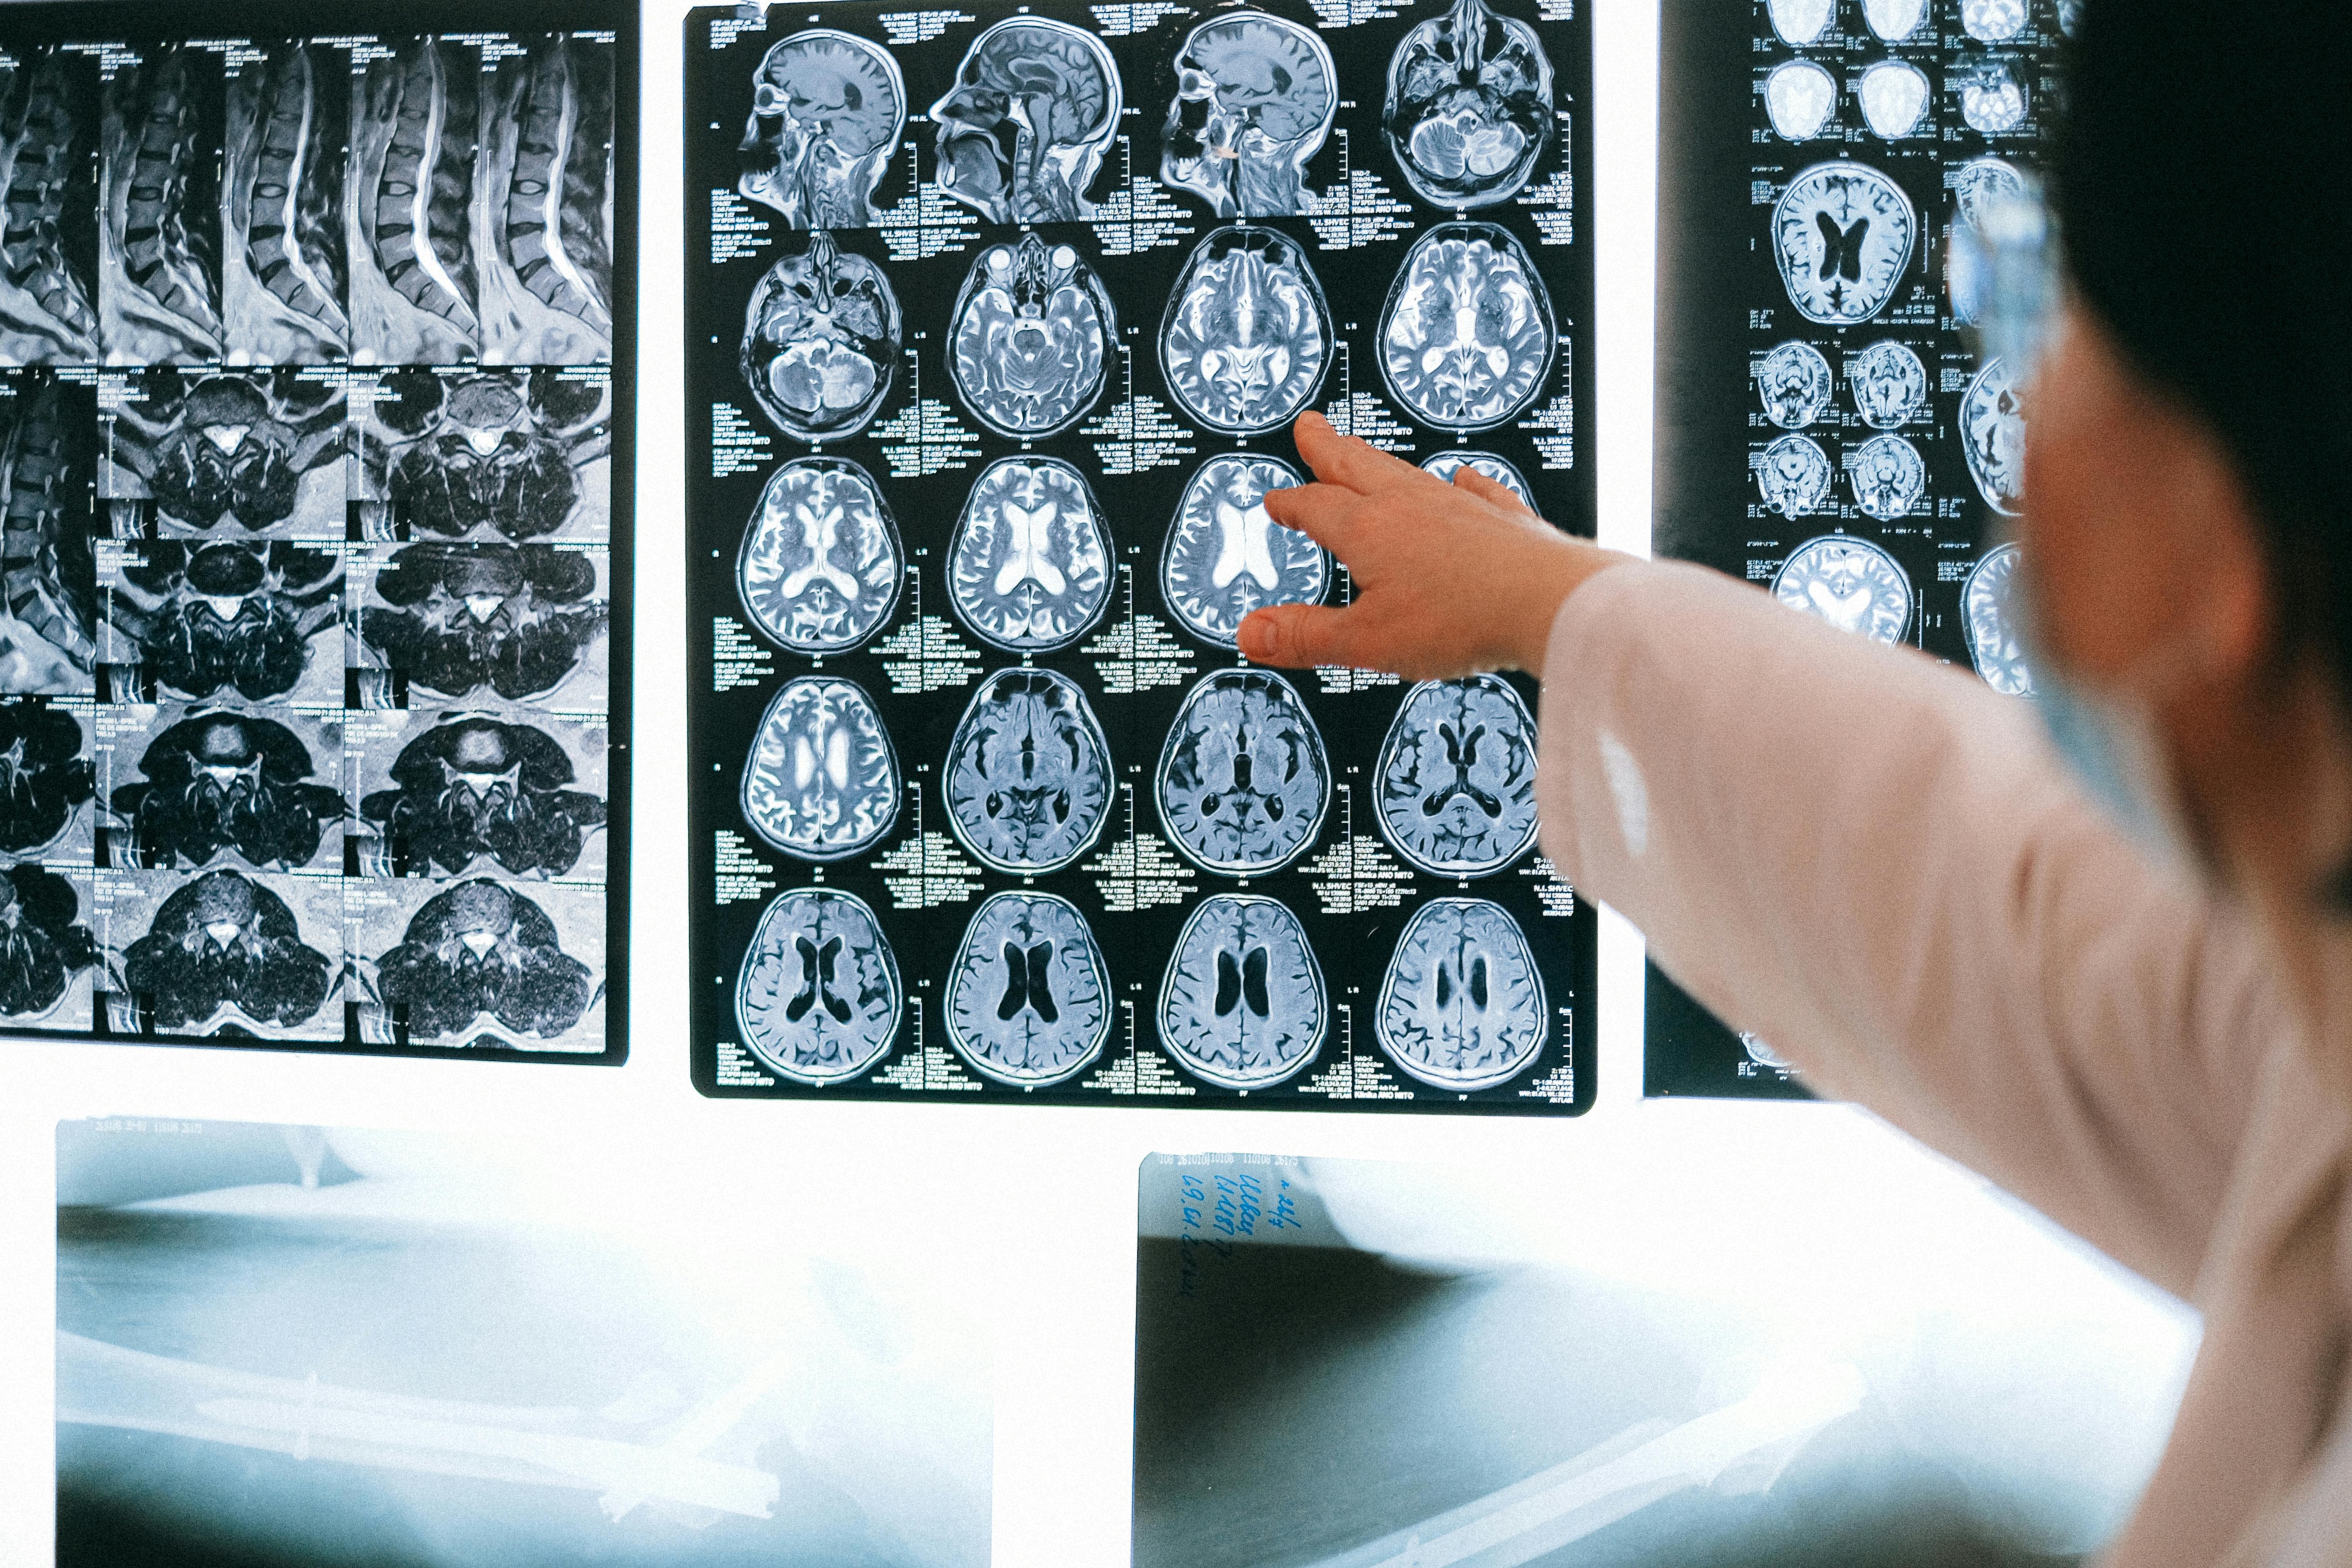

Notably, the recording was captured when an 87-year-old patient underwent cardiac arrest while being treated for epilepsy. A device strapped on the patient’s head managed to capture 900 seconds of brain activity around the time of death, allowing the doctors to observe what happened in the 30 seconds before and after his heart stopped beating.

The researchers saw changes in a specific band of neural oscillations, the so-called gamma oscillations as well as delta, theta, alpha, and beta.

Notably, brain oscillations, or brain waves, are repetitive patterns of electrical impulses normally present in living human brains. Gamma waves are involved in high-cognitive functions such as memory retrieval, which is associated with memory flashbacks.